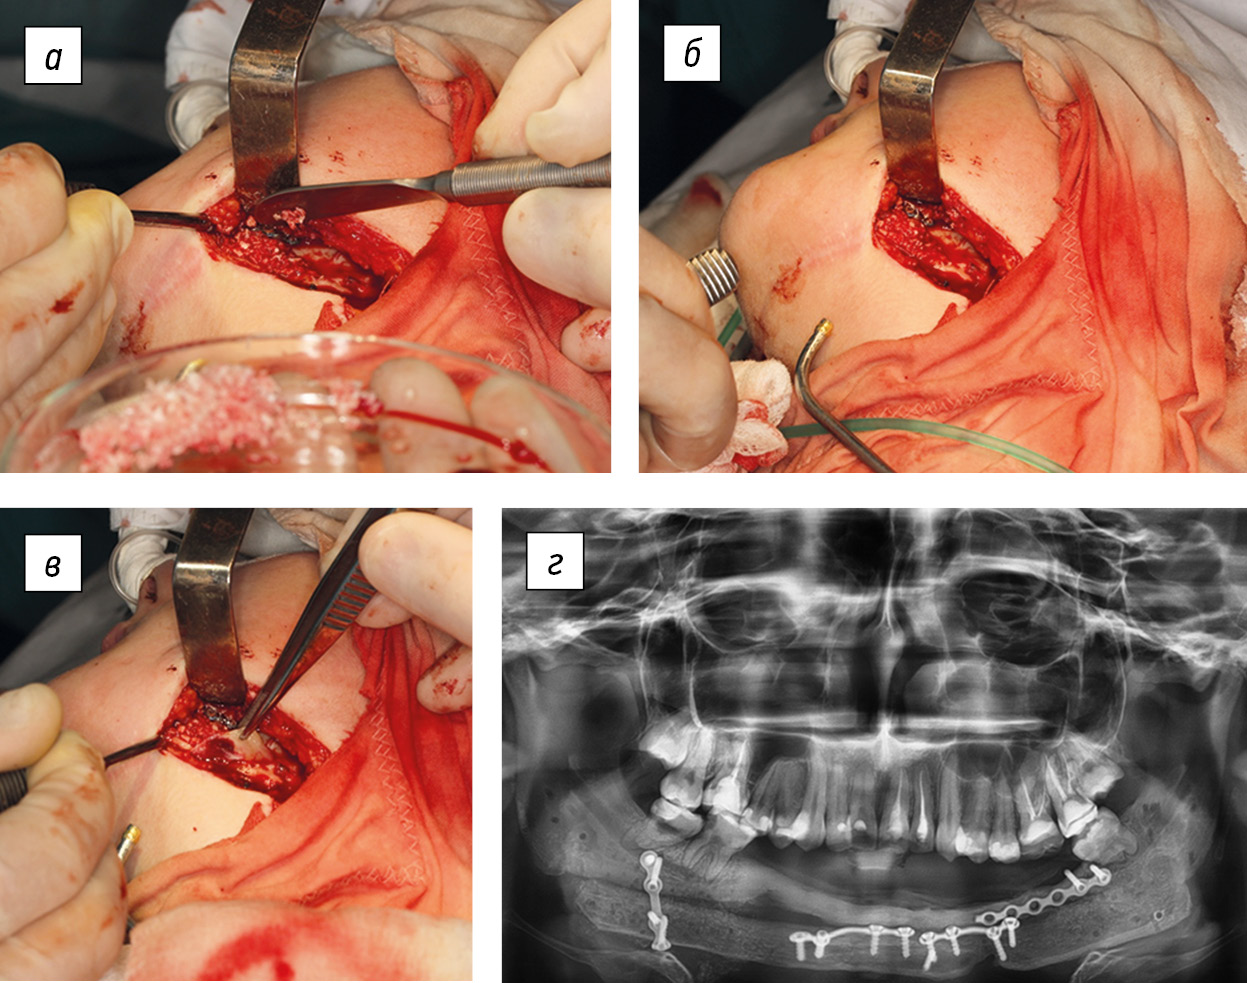

The surgery was performed in the Department of Maxillofacial Surgery of the Turner Scientific and Research Institute for Children’s Orthopedics by two teams of surgeons. One team prepared the receptive bed on the jaw after the removal of the titanium endoprosthesis and then modeled and fixed the bone graft on the jaw. Within 10 years of using a titanium endoprosthesis, under the action of masticatory muscles, a partial remodeling of the stumps of the resected fragments of the jaw occurred, and a bone “bridge” was formed between them. Team 2 of surgeons harvested the vascularized graft from the fibula and made anastomoses on the vessels of the graft and the receptive bed of the jaw. Thus, the surgery consisted of several successive stages, namely, skeletonization of the jaw with an endoprosthesis (the last one was removed), removal through an S-shaped incision in the projection of the fibula of the diaphysis, and addition of feeding vessels, namely, two veins and an artery with a diameter of up to 2.5 mm. Vessels were ligated and dissected, and a fibula fragment of 23 cm long was resected. Then, a transosseous canal was formed through the incision in the ankle area with fixation of the lateral ankle with a bone pin. Thereafter, an osteotomy, fragmentation of the bone graft according to the jaw template, and fixation of its fragments with mini-plates were performed. The integrity of the compact plate and periosteum on one side of the graft and, accordingly, the feeding vessels (arteries and veins) were preserved. The autogenous bone graft was placed along the edges of the fragments and on the surface of the jaw branches and fixed with five mini-plates with screws. Then, vascular anastomoses (9-0 Prolene) were placed between the proximal peroneal artery and the superior thyroid artery and between two more vessels of the donor and recipient zones. The patency test of the anastomoses was positive. Layered sutures were placed on the wound, with passive drainage (Fig. 6).

Fig. 6. Patient B (17 years old). Stages of bone grafting of the lower jaw with a vascularized fibula graft (a–d), and X-ray image of the immediate result of the surgery (e)